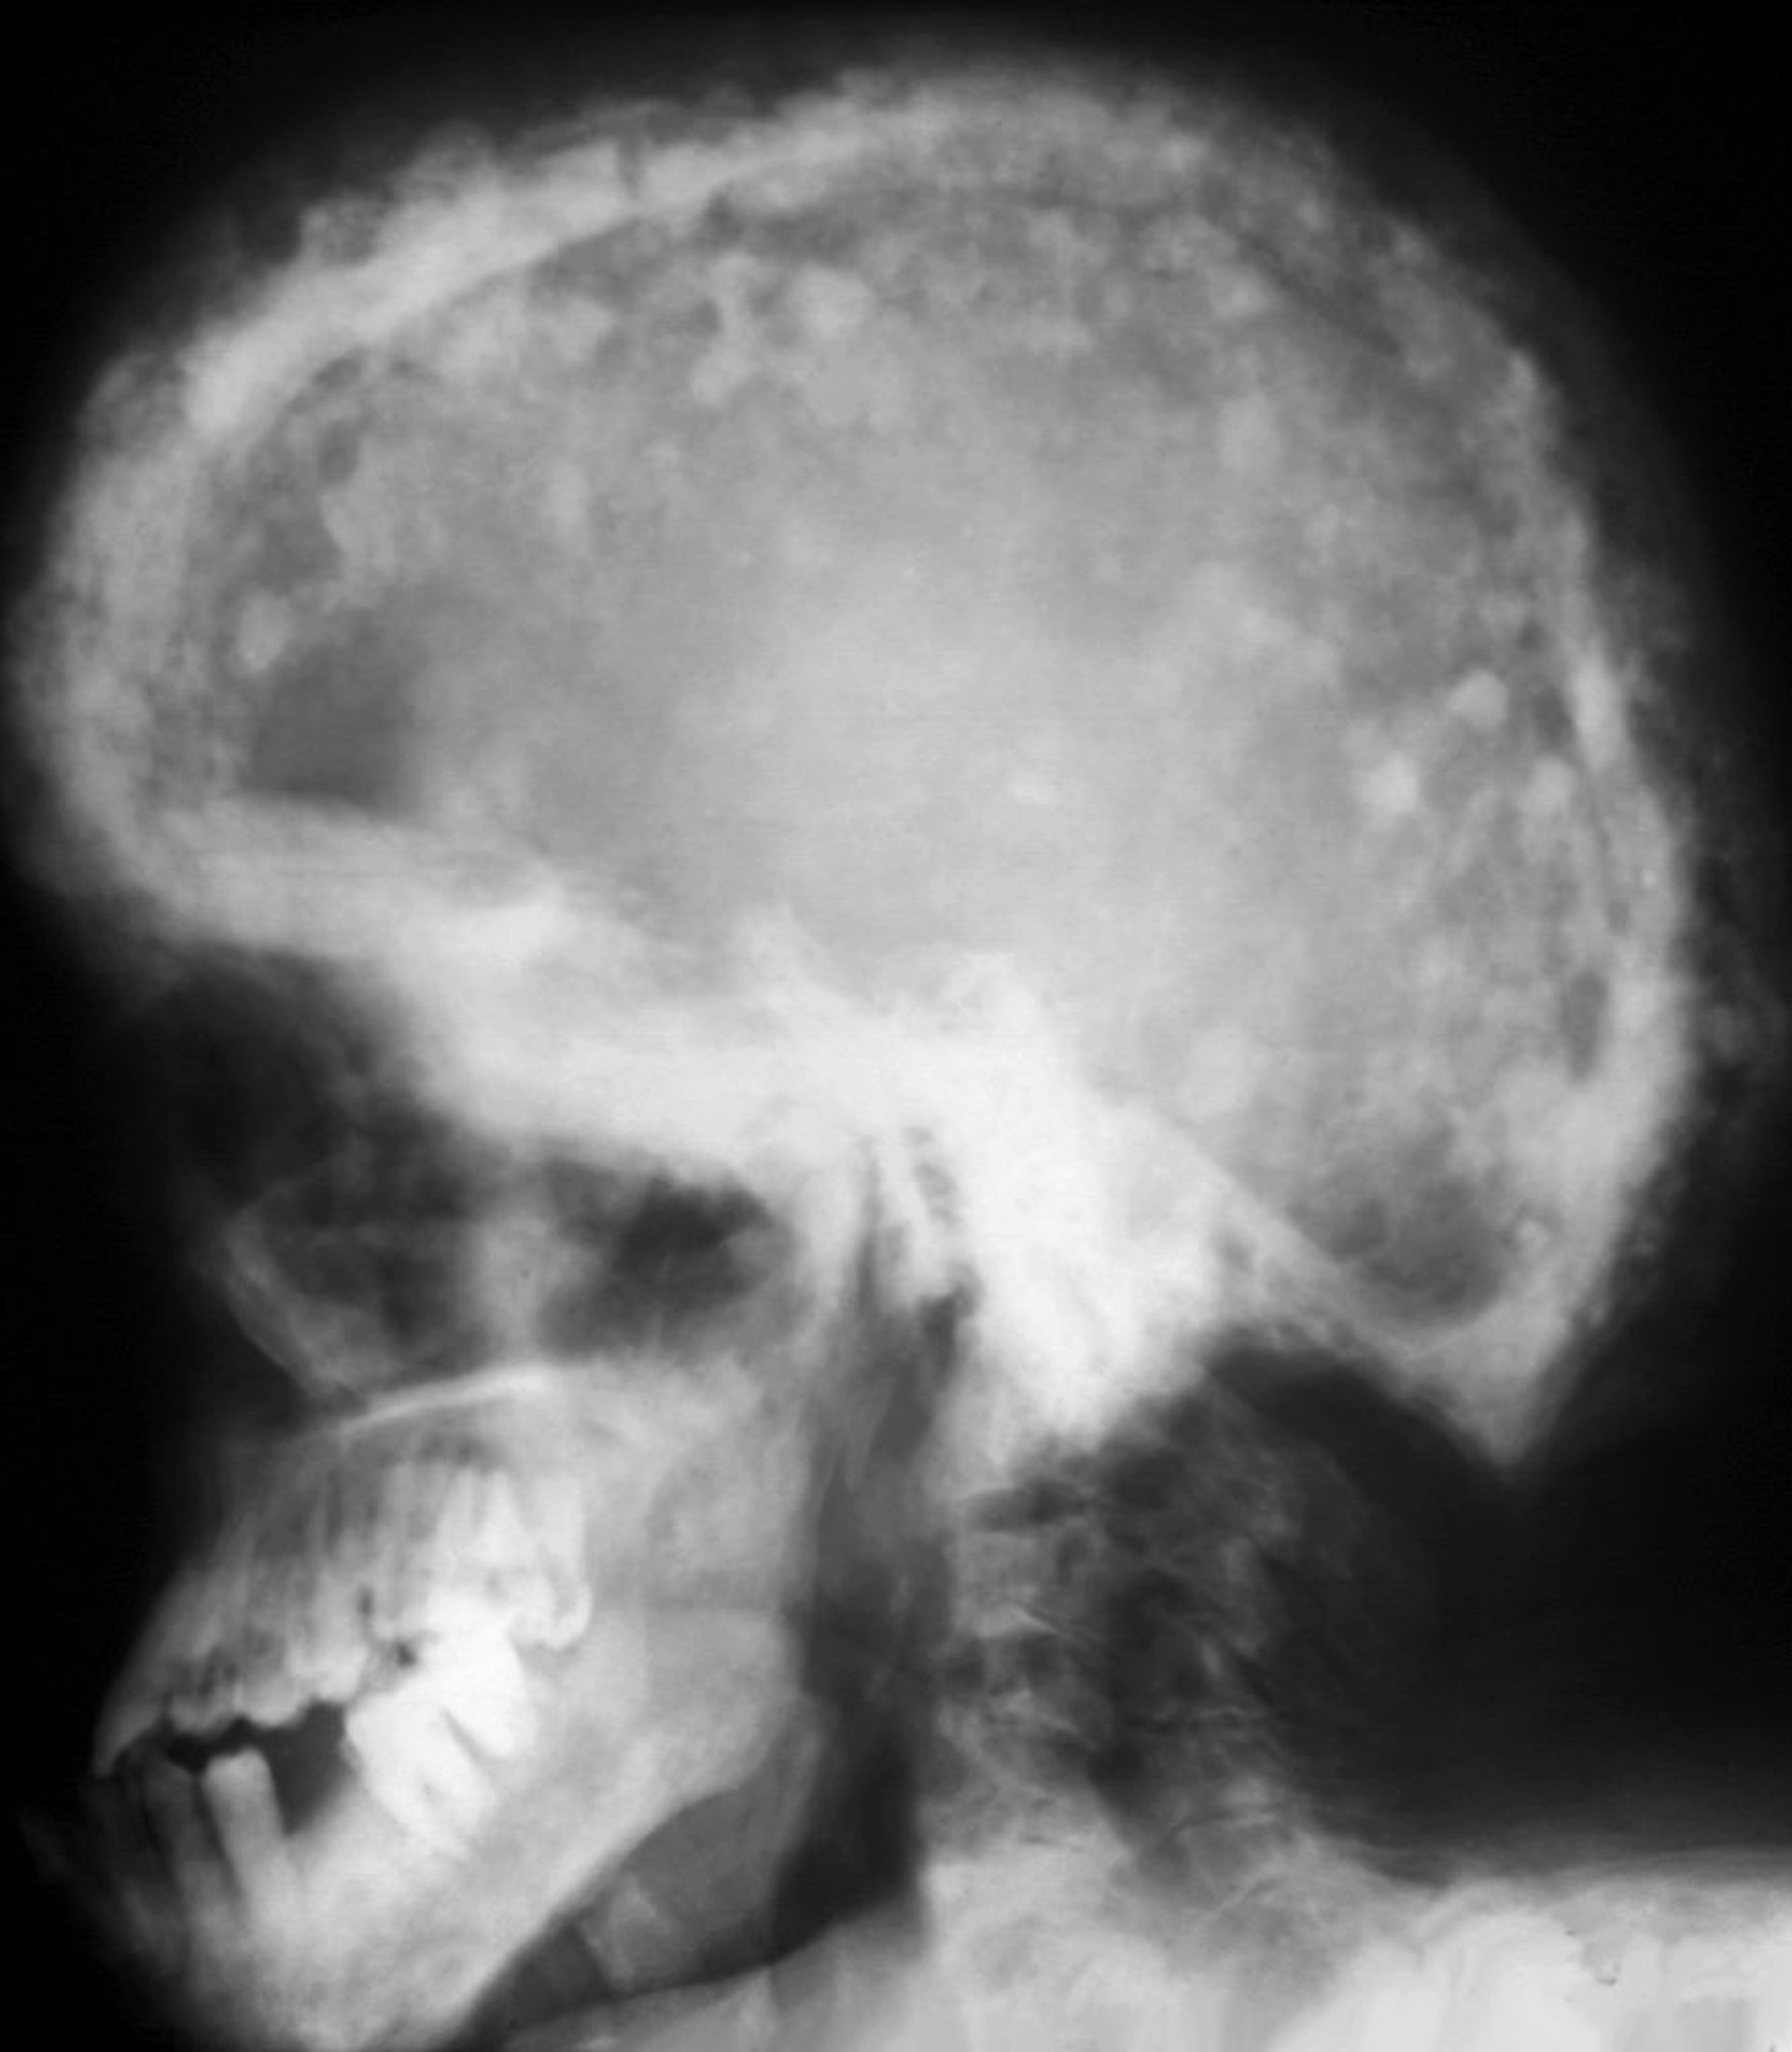

Radiografia do crânio na doença de Paget

Um padrão típico de mosaico das áreas de maior esclerose e lucência é visto nessa radiografia. Essas manchas de algodão hidrófilo resultam do espessamento da calota craniana.